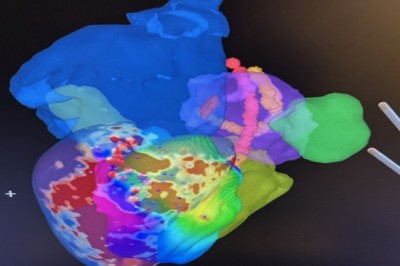

أول عملية استئصال عضلة القلب البطينية الإقفارية البشرية بنجاح في iCMR